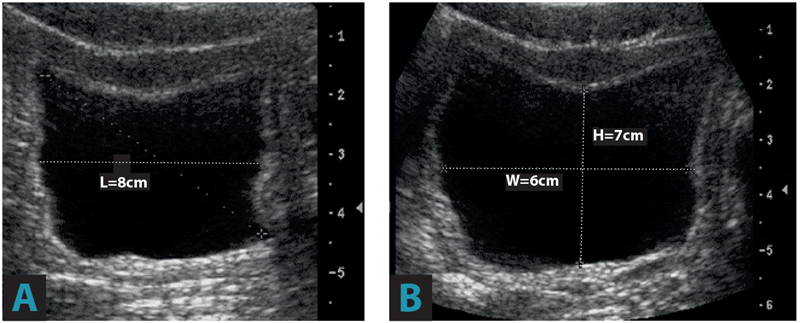

- Calculate the urine volume from the ultrasound images A and B.

By taking measurements in two planes, and deriving length, width and height measurement, bladder volume can be calculated. This utilises the prolate ellipsoid formula (π/6 x L x H x W). This is relatively simple and easy to use.

(π/6 x L x H x W) or more simply (0.52 x L x H x W) (prolate ellipsoid formula) = 175mls.